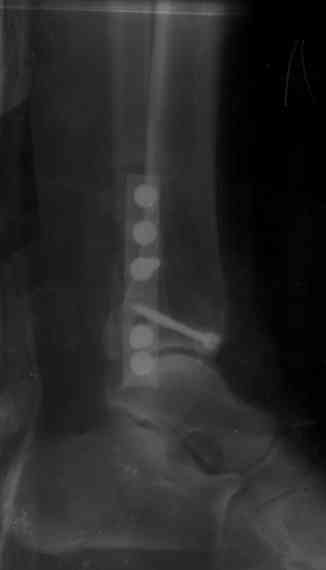

На 4-й неделе убрал спицы, с 7-й недели начал ЛФК, дозированную нагрузку, физиопроцедуры, массаж. Назначил хондропротекторы. Получилось вот что.

Rg-05.JPG

Удалены спицы, а гипса не было? 3-х лодыжечный перелом фиксировать 4 недели недостаточно. Что и подтверждается на последнем снимке - есть тенденция к подвывиху кнаружи, кзади... Что будет дальше, когда пациент начнет давать полную нагрузку?

Малоберцовая выглядит коротковатой. Профиль как-то мутный. Вообще, неплохо было бы сделать снимки в сравнении со здоровой.